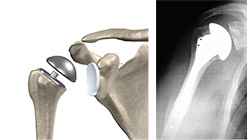

Protesi totali: sono indicate nelle patologie degenerative (srtrosi, artriti, ecc) e sono costituite da una componente omerale dotata di stelo per ancorarsi nel canale omerale e una parte glenoidea (impiantata nella glenoide scapolare) a diretto contatto con la testa protesica e costituita di materiale plastico. Le componenti protesiche possono essere fissate a incastro (press-fit) o cementandole con cementi ossei acrilici.